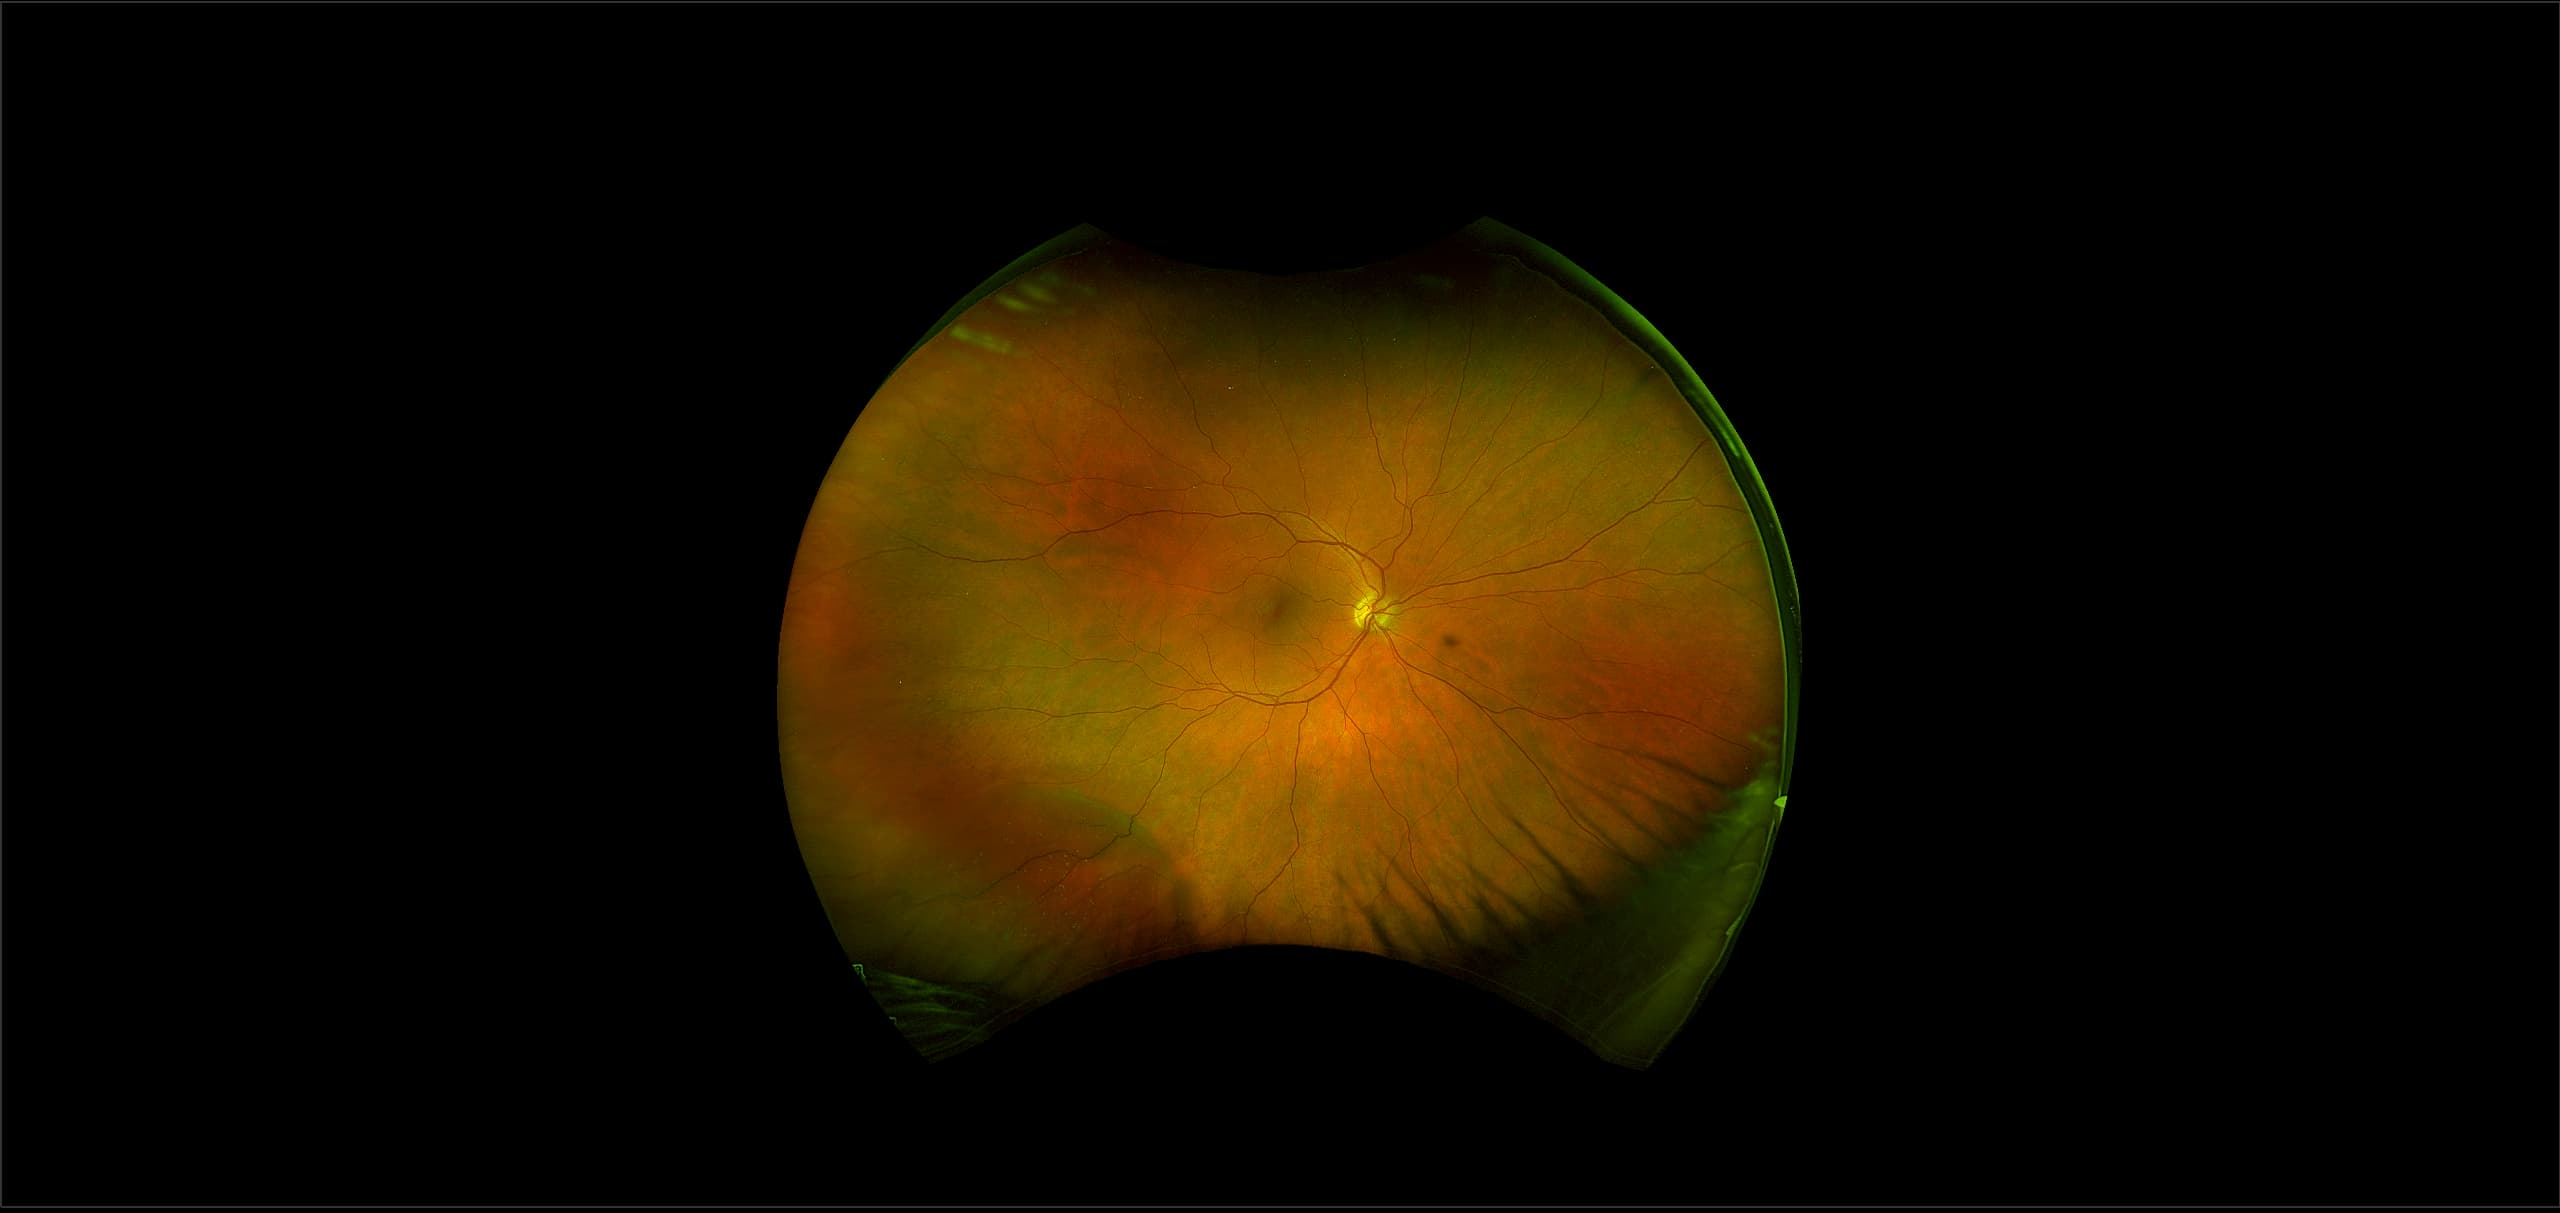

California - Retinoschisis, RG

A retinoschisis is a splitting of the sensory retina into 2 layers; an inner and outer layer. The etiology is most likely vitreous traction that physically pulls the retina apart. The posterior border of a retinoschisis is convex to the posterior pole, because a retinoschisis forms like blowing up a balloon in the peripheral retina (as seen in most retinal detachments).The inner layer can be shallow or bullous into the vitreous cavity. The inner layer may or may not have retinal vessels in it (depending if the retinal vessels pass into the inner layer or outer layer). Since the vessels in the inner layer are above the retinal surface like vitreous floaters, they can block the exiting light and produce a shadow effect dark vessels .